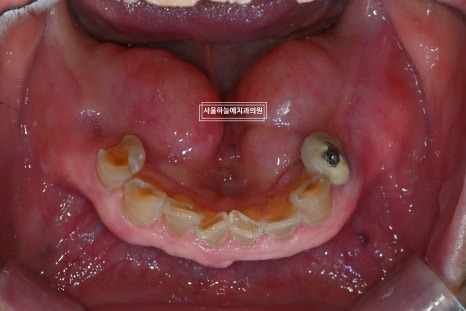

아래 양쪽 어금니가 오래전부터 없는 상태였고

앞니는 부러져 식사가 불편하셨으며,

오랜 기간 치아가 없었던 영향으로

위아래 치아 공간이 거의 사라진 상태였습니다.

아래 어금니가 없는 기간이 길어

위 치아와 잇몸이 맞닿을 정도로 공간이 부족,

아래 앞니 역시 심하게 마모된 상태였습니다.